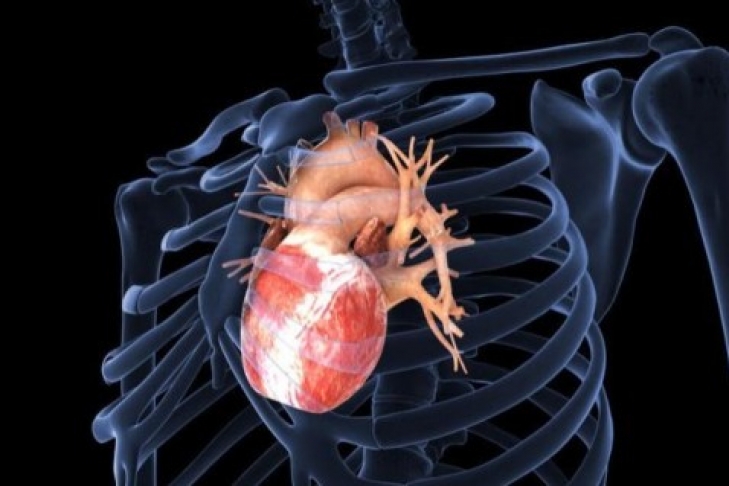

Украинские специалисты разработали новый тип сердечного клапана

Украинские ученые создали уникальный тип сердечного клапана из нитинола, сконструированный по принципу Геймлиха, который позволит удешевить операции по их имплантации в десятки раз, сообщает Укринформ.

По словам профессора Ильи Емца, специалисты Института металлофизики им Курдюмова совместно с учеными НАН Украины уже обсуждают вопрос создания медико-инженерного центра.

"Нитинол - это сплав никеля и титана, обладающий "эффектом памяти формы". То есть он может восстанавливать заданные параметры при нагреве, например, обретая форму ажурной конструкции внутри сосуда. Ныне широкой доступности метода препятствует его дороговизна. Например, в Мюнхене операция стоит минимум 40 тысяч евро, причем львиная доля этой суммы приходится на высокотехнологичный имплантат", - рассказал специалист.